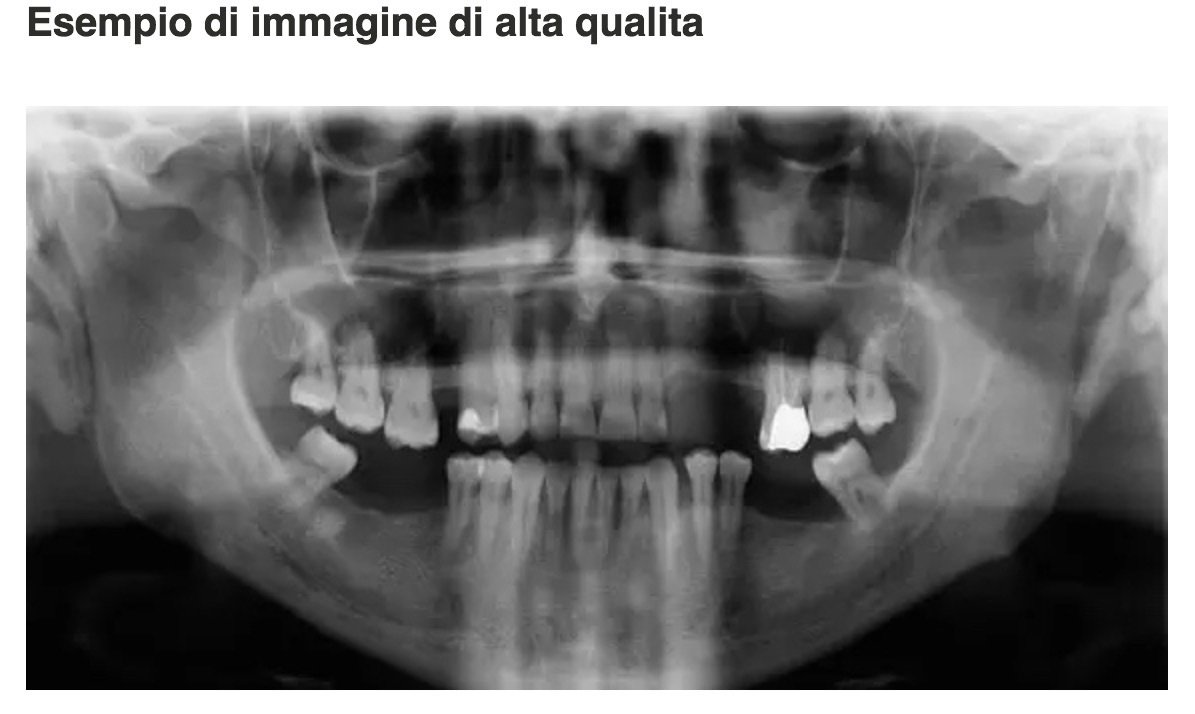

About Dentista in Moldavia La nostra struttura, la Clinica Stomatologica a Chisinau (Moldavia), offre il più ampio panorama nel settore delle cure dentali: , Chirurgia Orale, Protesi fissa, Protesi mobile, Protesi semifissa, Paradontologia, Odontoiatria Conservativa, Odontoiatria Estetica (, Otturazione Estetiche, Gioielli Dentali), Endodonzia, Pedodonzia e Radiologia. Sicurezza, garanzia di qualità e tecniche di avanguardia: tutto q... (Show more)